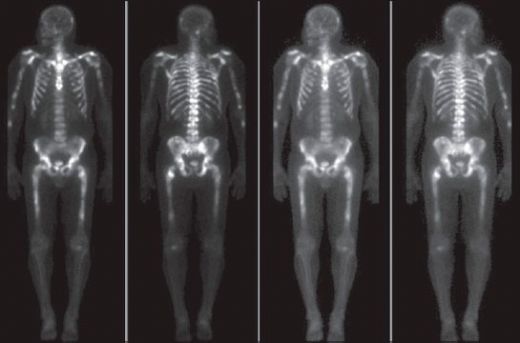

Kemik Metastazı Tanısı Kemik metastazının tanısı, çeşitli tıbbi testler ve görüntüleme yöntemleri ile konulmaktadır. Bu testler şunlardır: